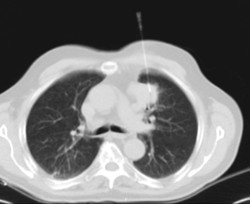

- TC Tórax

Prueba diagnóstica que consiste en obtener imágenes del tórax de alta definición anatómica (pulmones, corazón, mediastino, grandes vasos, caja torácica, etc.) mediante el empleo de un equipo de TC (Tomografía Computarizada). Dichas imágenes se estudian posteriormente en una estación de trabajo que permite reconstrucciones bidimendionales en diferentes planos del espacio y también reconstrucciones 3D (volumétricas). Algunos estudios requieren el empleo de contraste yodado para mejorar la definición de las imágenes. - Angio-TC Aorta torácica

Prueba radiológica que consiste en obtener imágenes del cuello de alta definición anatómica mediante el empleo de un equipo de TC (Tomografía Computarizada). Indicaciones: infecciones, abscesos, estudio ganglios. - TC Tórax

Prueba diagnóstica que consiste en obtener imágenes del tórax de alta definición anatómica (pulmones, corazón, mediastino, grades vasos, caja torácica, etc.) mediante el empleo de un equipo de TC (Tomografía Computarizada). Dichas imágenes se estudian posteriormente en una estación de trabajo que permite reconstrucciones bidimendionales en diferentes planos del espacio, y también reconstrucciones tridimensionales (3D: volumétricas). Algunos estudios requieren el empleo de contraste yodado para mejorar la definición de las imágenes. - TC Abdomen